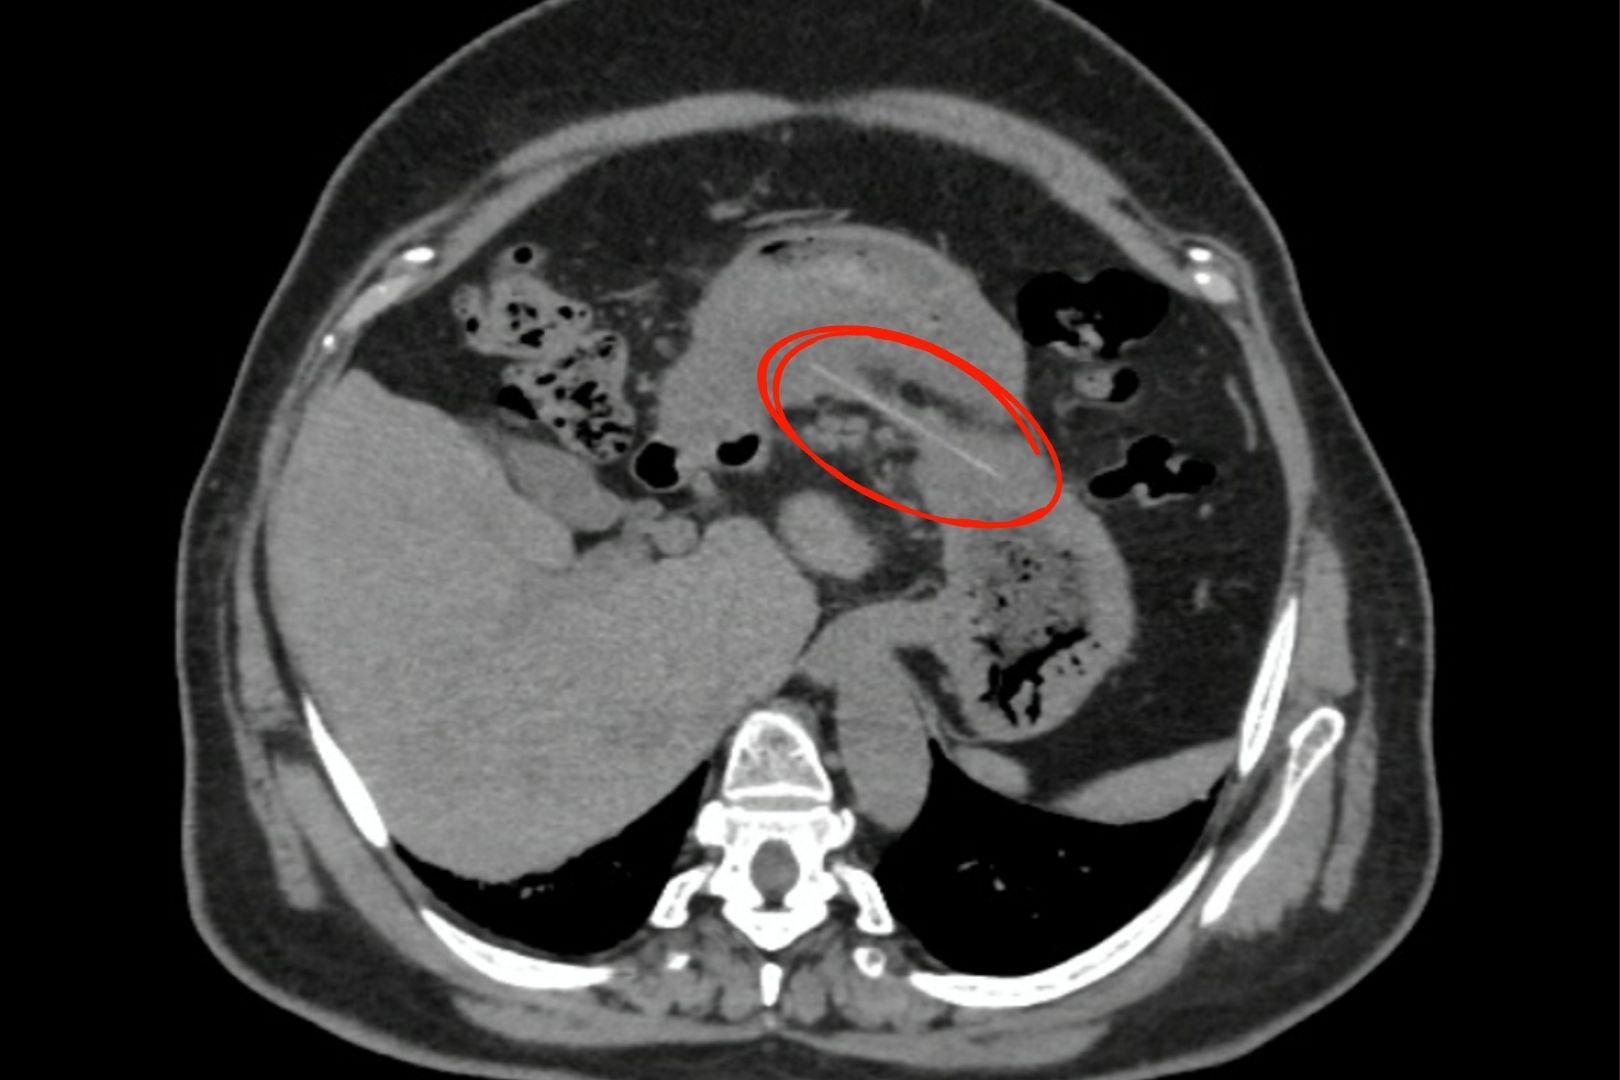

Qua quá trình thăm khám và nội soi, các bác sĩ phát hiện một khối áp xe ở thành dạ dày. Nhận thấy dấu hiệu bất thường, bệnh nhân được chỉ định chụp CT-scan. Kết quả hình ảnh đã xác nhận có một dị vật hình que, sắc nhọn đã đâm xuyên qua thành dạ dày và đi vào trong ổ bụng.